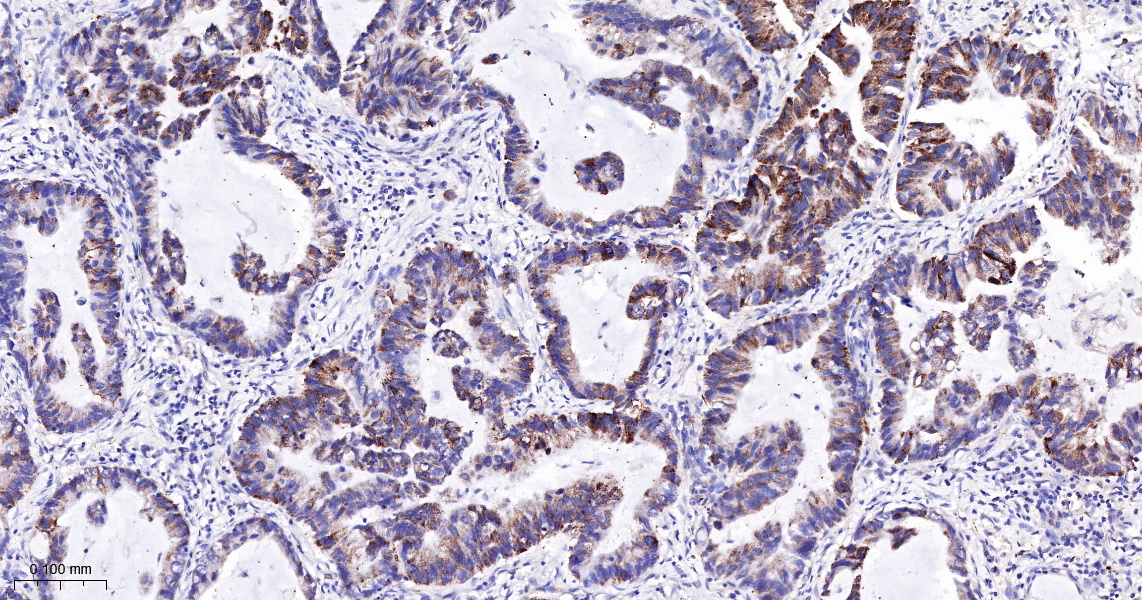

IHC-P 1:200-400